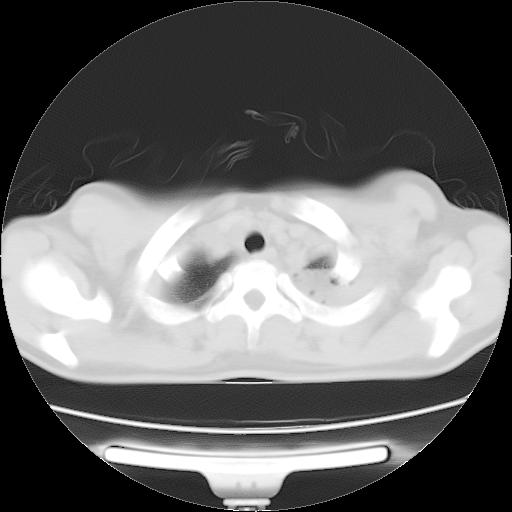

女,29岁,胸部不适,在外院胸片提示胸腔积液,到我院ct检查。

纵膈窗